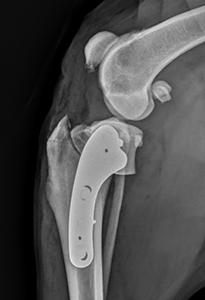

Dr. Alexander Davies BVSc PGCertSAS PgC(SADI) MRCVS leads our orthopaedic referral service at Sandhole Vets.

Alex is an advanced veterinary practitioner in small animal surgery. He has a certificate in Small Animal Surgery and a second in Diagnostic Imaging. He has experience with TPLOs, fabellotibial sutures, patella surgery, and most standard to moderately complex fractures. Alex is also experienced and comfortable with diagnostic work-ups of complicated orthopaedic cases, as well as soft tissue experience such as TECA/LBOs, BOAS patients, abdominal biopsies, and intestinal/urinary surgeries. Alex is happy to review images and cases with referring vets, and is happy to discuss if he can also help in more complex cases.